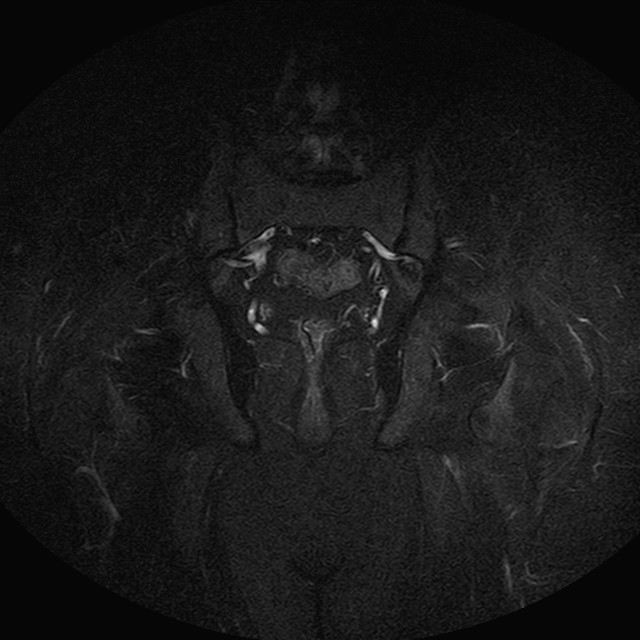

eSTIR

Evidenti e simmetriche alterazioni osteofitosiche in regione coxo femorale con riduzione delle rime articolari. Degenerazione completa del cercine glenoideo. Non attuali segni di versamento articolare. Non segni di edema osseo che escludono attuale algodistrofia od osteonecrosi. Lieve e simmetrica riduzione del trofismo della muscolatura glutea.